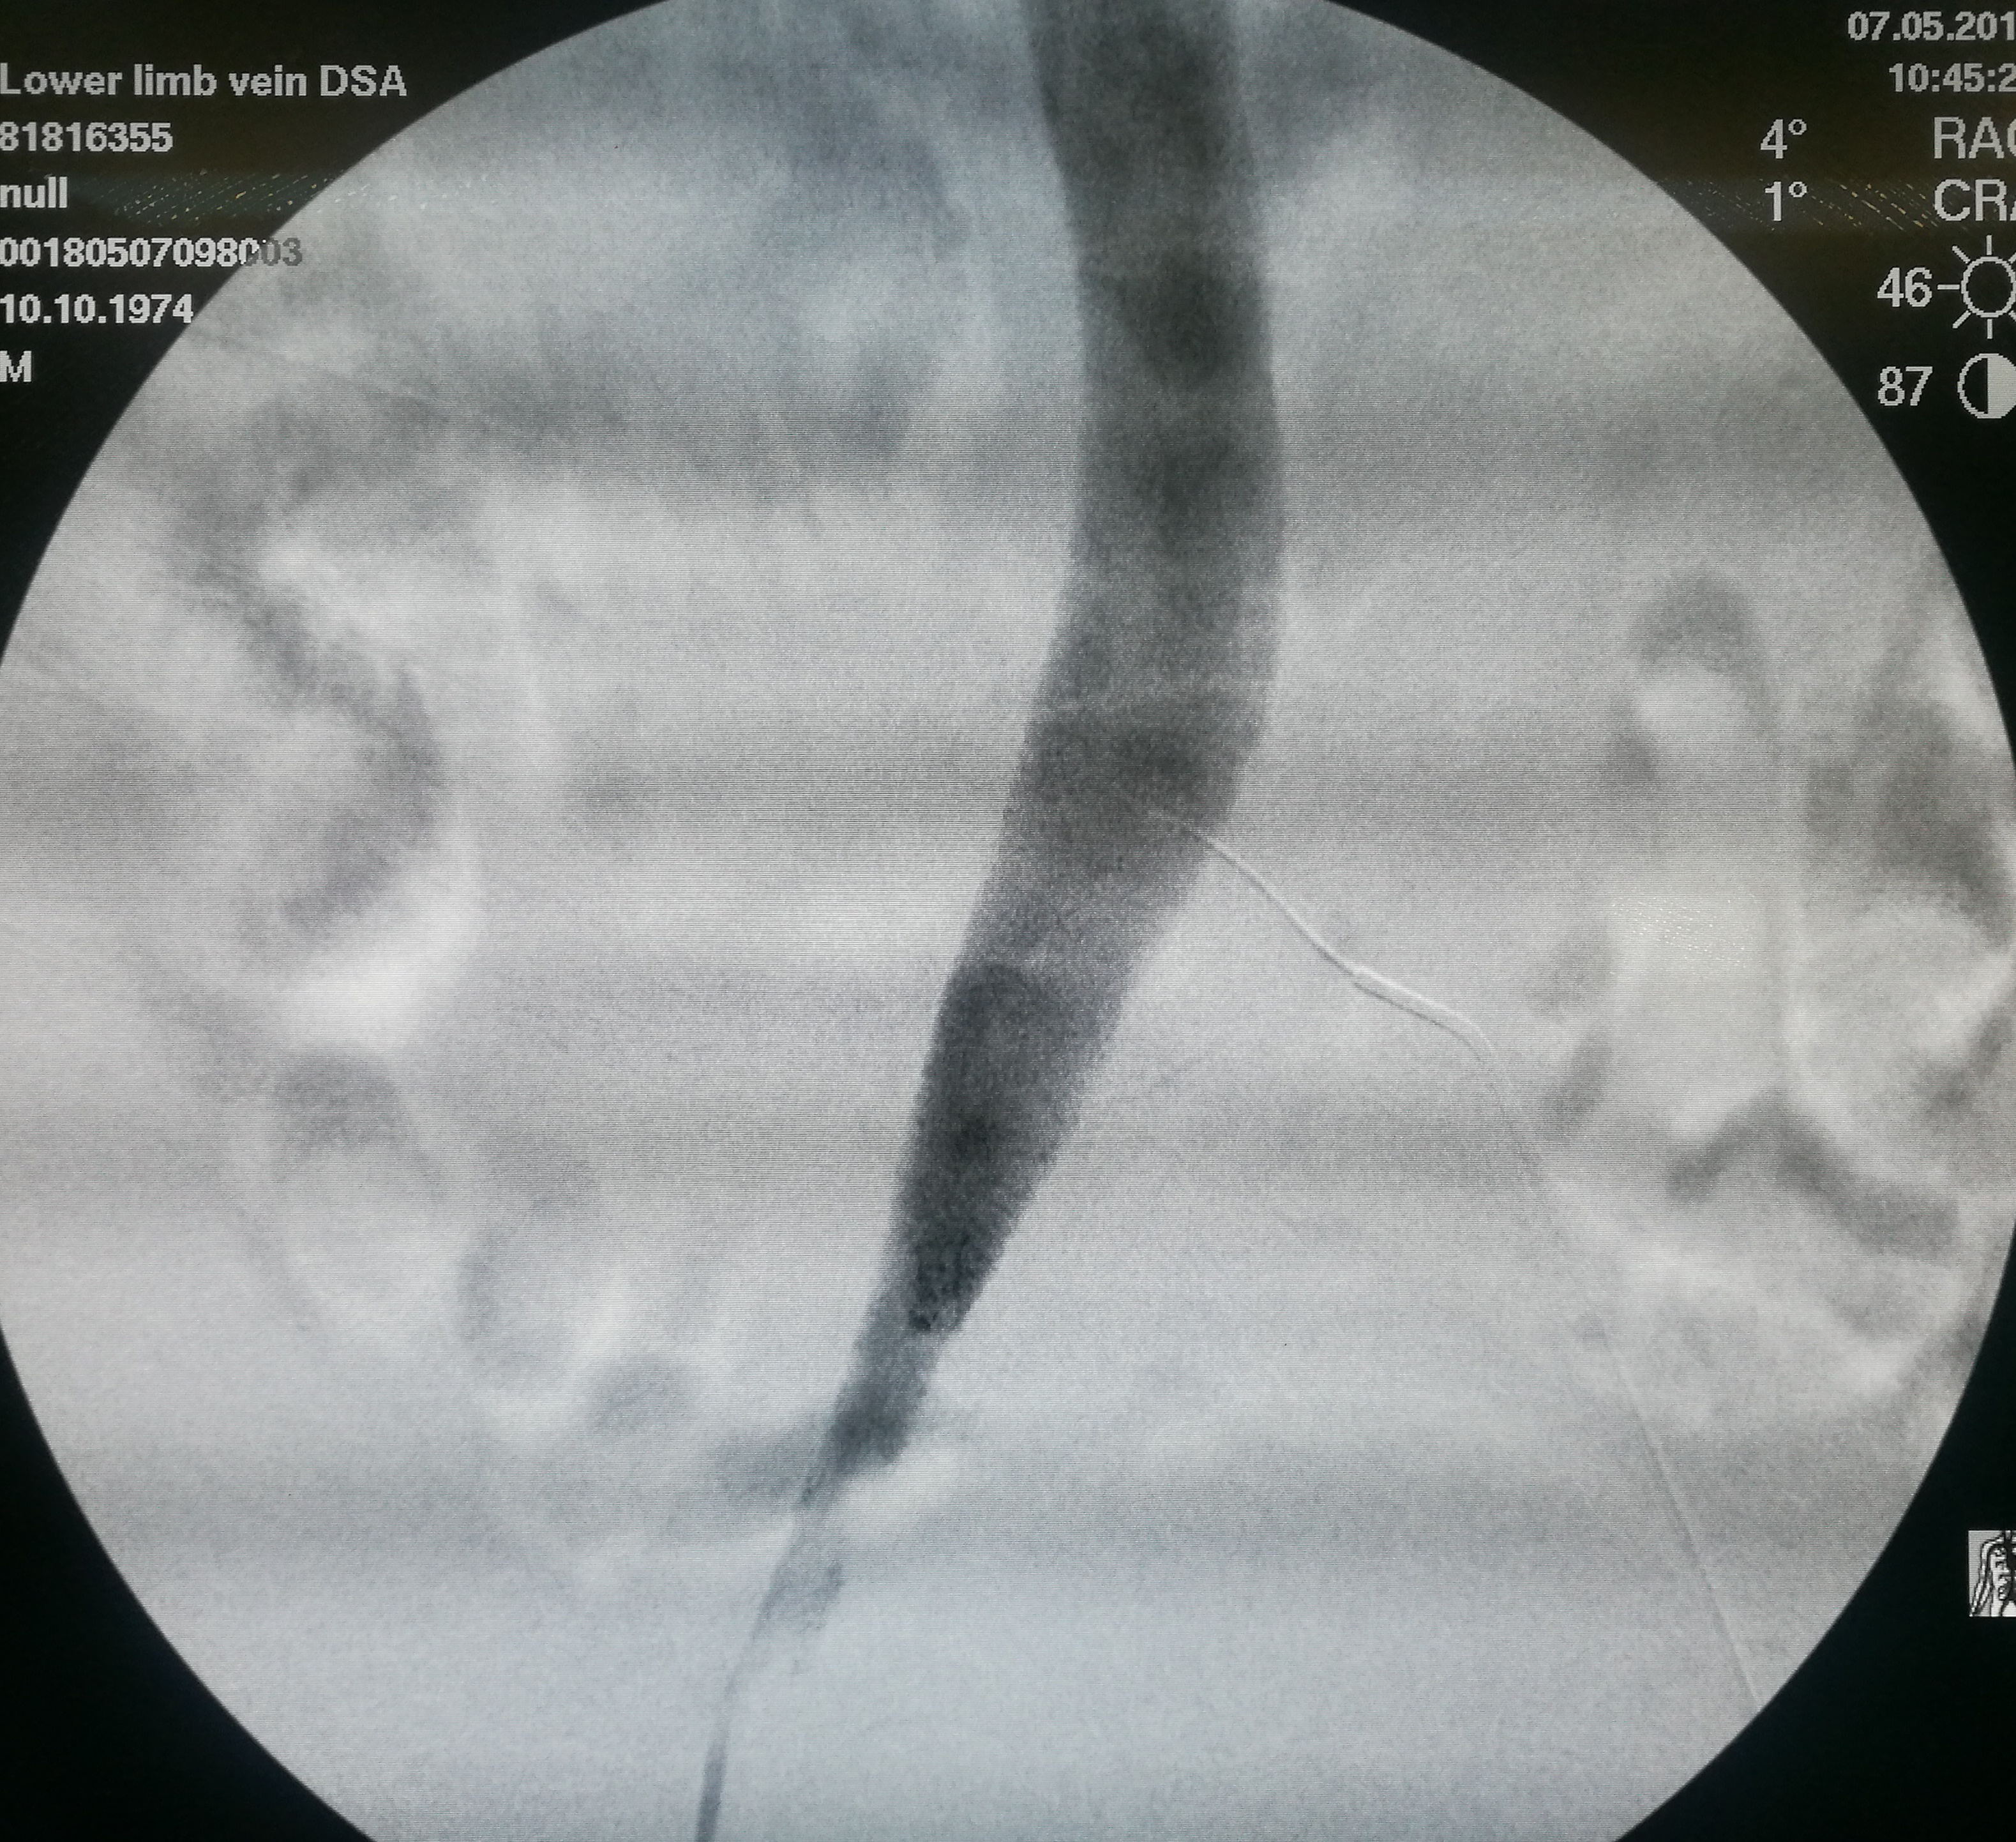

第三个患者是昨天做的,也是反复左下肢深静脉血栓,最近又发作。本次在超声引导下使用肝穿针穿刺左股静脉(其内充满血栓,盲穿无回血),配合超滑导丝,艰难前行约7-8cm后送入血管鞘,之后用导管导丝配合,进入到中线右侧,但从导丝头端的活动度看,未能回到下腔静脉。穿刺右侧股静脉,用SIM1导管从下腔静脉内逆行钩选左侧髂总静脉,在髂总远侧实现和左侧导管的对接,建立真腔轨道。之后在下腔静脉内植入滤器,再对左侧髂总、髂外静脉进行扩张,植入支架。

在下腔静脉内留置滤器

植入的支架